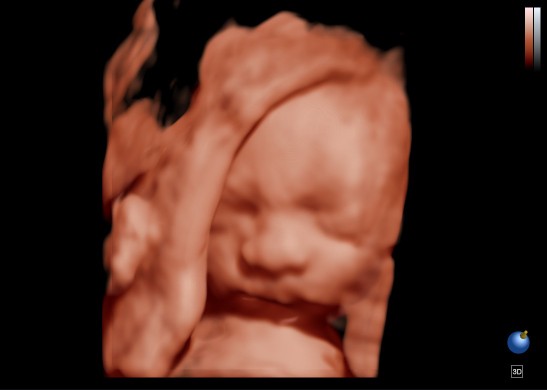

บ้านนี้เอาเท้ายัดใส่ปากโชว์เลยคร้าาา❤️